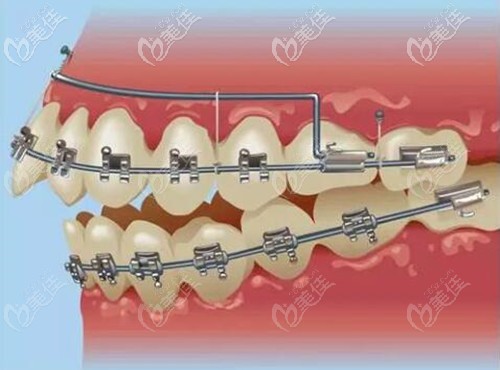

種植牙是缺幾顆就要種幾顆嗎?全口無(wú)牙豈不是要種28顆牙?有什么方法可以少種植點(diǎn)嗎?其實(shí)還真有,今天我們就來(lái)了解一下!... b1596 G0 V0